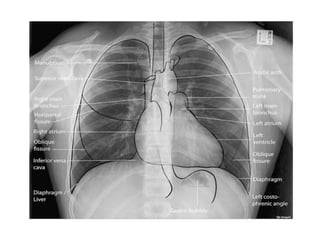

Normal Chest X-Ray

Scheme of viewing PA film

1. Request form                Name ,age, sex, date, clinical information

2. Technical                   View

Centering, patient position

Side Markers

Adequate inspiration

Exposure/Penetrance

3. Soft tissue and bony cage   Subcutaneous emphysema, fractures

4.Trachea                      Position, Outline

5. Heart and Mediastinum       Shape , Size, Displacement

6.Diaphragms                   Outline ,Shape , Relative position

7.Pleural spaces               Position of horizontal fissure,

costophrenic and cardiophrenic angles

8.Lungs                        Local , generalized abnormalities,

comparison of translucency and vascular

marking sof the lungs

9.Hidden areas            Apices, Posterior sulcus, Mediastinum,

Hila, Bones

10. Hila                  Density, Position, Shape

11. Below the Diaphragm   Gas shadows, Calcification